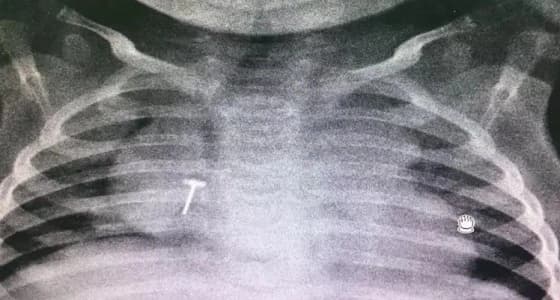

تمكنت مدينة الملك سعود الطبية، ممثلة في طوارئ مستشفى الأطفال، من إنقاذ طفل رضيع ابتلع قطعة معدنية، حيث قام فريق طبي متخصص في جراحة الصدر لدى الأطفال، باستخراج القطعة من رئة الطفل.

حيث أكدت المدينة، أن الأشعة أظهرت وجود القطعة المعدنية في الرئة اليمنى للطفل، مما سبب له مشاكل تنفسية، مشيرة لأن الطفل في حالة صحية جيدة، ويستعد للخروج من المستشفى.